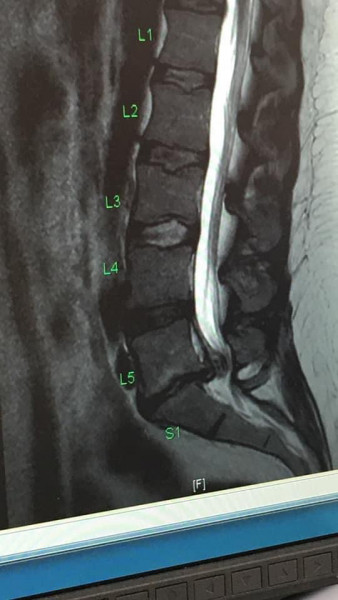

anotherdaynotanotherdollar · 30/04/2022 14:56

This was before my first op. Second 2 scans before ops were the same so pointless putting them up. I'll also post one that shows how it was after my last op.

Could this be cauda equina